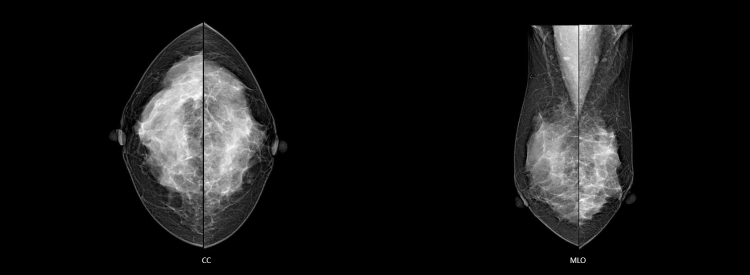

Tam işlevsel görüntü tanısı ve akıllı entegre görüntü alma sağlayan profesyonel iş istasyonu, kullanıcılara rahatlık sağlarken aynı zamanda özel görüntü işleme algoritması sayesinde yüksek kaliteli görüntüler sunar.